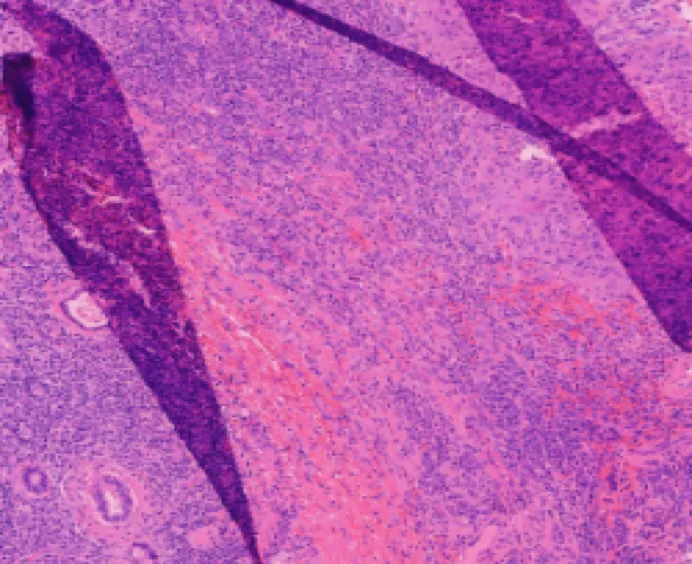

Identify Pattern

1. Benign follicular nodule

2. Undetermined follicular disease

3. Suspicious for follicular tumor

4. Suspicious for malignancy tumor

5. Papillary thyroid carcinoma